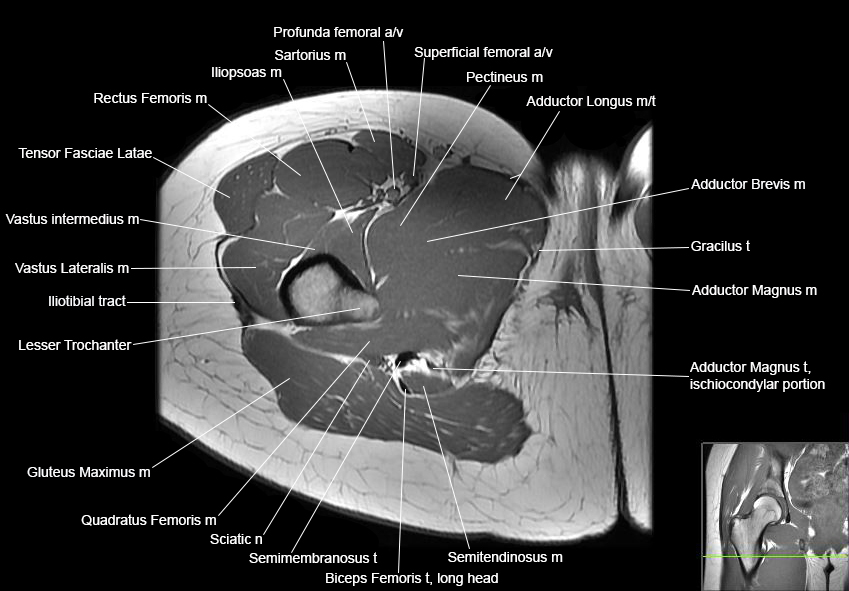

Hip

Basic Hip MRI

MRI Hip Anatomy

Scroll using the mouse wheel or the arrows